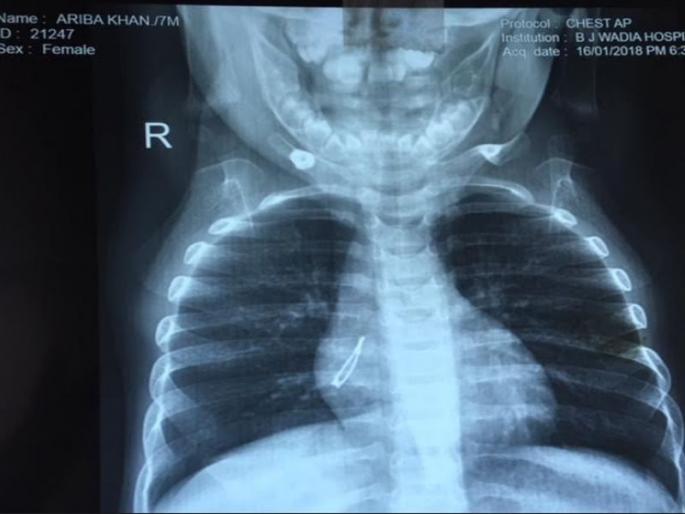

मुंबई - चिपळूणमध्ये राहणाऱ्या ७ महिन्याच्या अरिबाने खेळता खेळता चुकून एलईडी बल्ब गिळला. पालकांना वाटले की तिने, दोरा किंवा मोबाईलची पिन गळली असावी. त्यानंतर तिला सतत खोकला आणि ताप येऊ लागला. त्यामुळे पालक तिला स्थानिक डॉक्टरांकडे घेऊन गेले, पण परिस्थितीत काहीही बदल झाला नाही. तिच्या उजव्या बाजूच्या फुफ्फुसामध्ये बाह्यघटक असल्याचे तिच्या एक्स-रेमध्ये आढळन आले. त्यानंतर आठवड्याभराने त्यांनी अरिबाला बाई जेरबाई वाडिया बालरुग्णालयात दाखल केले असता डाँक्टरांनी कुठलाही वेळ न दवडता तपासणी करून ब्लाँन्कोस्कोपीने अगदी २ मिनिटांत हा बल्ब बाहेर काढण्यात यश आलं.

बाई जेरबाई वाडिया हॉस्पिटलमधील ईएनटी (कान-नाक-खसा) विभागाचे प्रमुख डॉ. दिव्या प्रभावत म्हणतात, "प्रतिजैविके देण्यात आली आणि जेव्हा ब्रॉन्कोस्कोपी केली गेली तेव्हा तो बाह्यघटक बरेच दिवस तिथे राहिल्याने संपूर्ण फुफ्फुसामध्ये कणिका उती (उतीचे कण) आढळून आली. हा संसर्ग काढून घालवून टाकण्यासाठी इंट्राव्हेनस (थेट नसेमधून) प्रतिजैविके आणि स्टेरॉइड्स देण्यात आली. त्यानंतर पुन्हा एकदा ब्रॉन्कोस्कोपी केली आणि दोन मिनिटांत हा बाह्यघटक (स्कोपमधून केवळ एक वायर दिसत होती) फोरसेप्सचा वापर करून काढण्यात आला. आश्चर्य म्हणजे तो २ सेंटिमीटरचा एलईडी बल्ब होता. इथे हजारच्या वर स्कोपी झाल्या आहेत, परंतु, त्यात असे कधीही आढळून आलेले नाही."